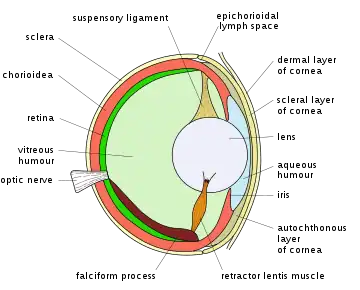

Schematic diagram of the human eye. | |

Position in the eye

The lens is located towards the front part of the vertebrate eye called the anterior segment which includes the cornea and iris positioned in front of the lens. The lens is held in place by the suspensory ligaments (Zonule of Zinn),[1] attaching the lens at its equator to the rest of the eye[2][3] through the ciliary body. Behind the lens is the jelly-like vitreous body which helps hold the lens in place. At the front of the lens is the liquid aqueous humor which bathes the lens with nutrients and other things. Land vertebrate lenses usually have an ellipsoid, biconvex shape. The front surface is less curved than the back. A human adult the lens is typically about 10mm in diameter and 4mm thick though changes shape with accommodation and size due to grow throughout a person's lifetime.[4]